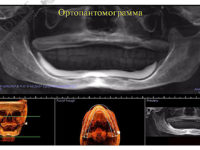

На фото представлен клинический случай в котором гребень практически полностью атрофирован, его попросту нет… В таких случаях, еще на этапах диагностики, необходимо учитывать те факты, что возникнут проблемы не только с фиксацией протеза на челюсти, но и возможные боли при ношении. Так как мы наблюдаем обнажение нерва в пределах протезного ложа, в мягких тканях нижней челюсти.

Проведя расчеты на основе ТРГ, мы обнаруживаем что нижняя челюсть данной пациентки имеет дистальное положение, следовательно когда происходит регистрация центрального положения на основе восковых шаблонов, должно быть принято решение в каком соотношении производить протезирование, оставить данное либо найти другое..